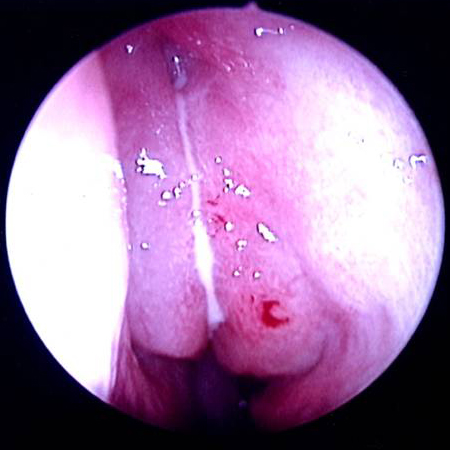

[Figure caption and citation for the preceding image starts]: Tomografia computadorizada com opacificação do seio nasal etmoide direito e abscesso orbital adjacenteDo acervo de Melissa Pynnonen, MD [Citation ends].